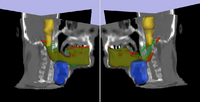

Adaptive Radiotherapy for Head, Neck and ThoraxWe proposed an algorithm to include prior knowledge in previously segmented anatomical structures to help in the segmentation of the next structure. This will add enough prior information to allow the Graph Cuts algorithm to segment structures with fuzzy boundaries. More... New: I. Kolesov, V. Mohan, G. Sharp and A. Tannenbaum. Coupled Segmentation for Anatomical Structures by Combining Shape and Relational Spatial Information. MTNS 2010.